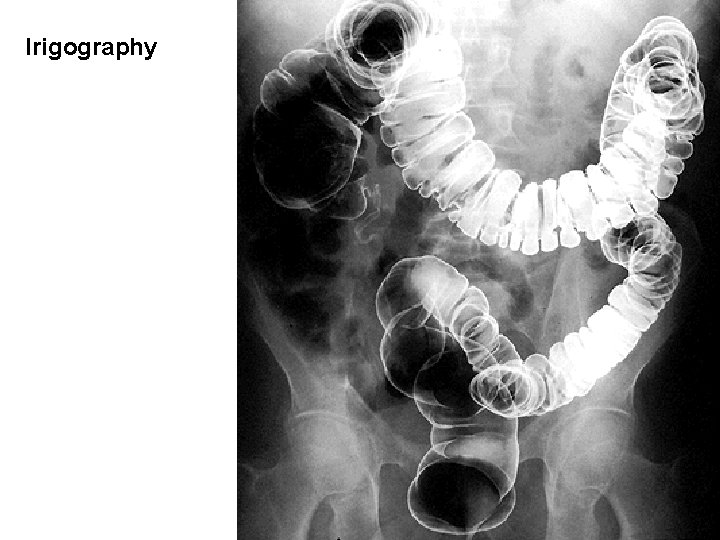

Irigography

RECTUM Crena ani – anus Ampulla recti - flexura sacralis - plicae transversae recti - plica t. r. media (Kohlrausch) Canalis - flexura perinealis - linea anorectalis - columnae anales - sinus anales - valvulae anales - pecten analis - linea anocutanea - zona haemorrhoidalis